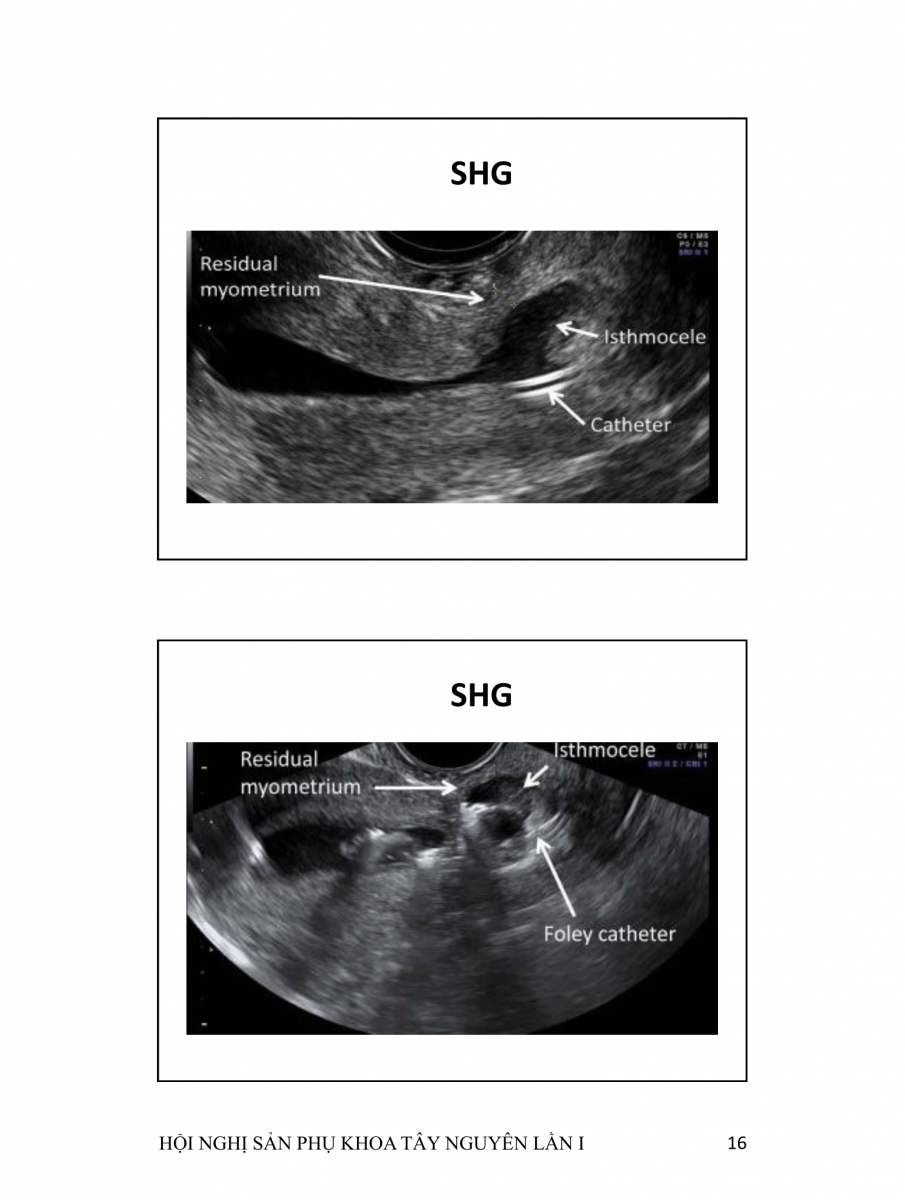

Hở khuyết sẹo mổ lấy thai  (CESAREAN SCAR DEFECTS)